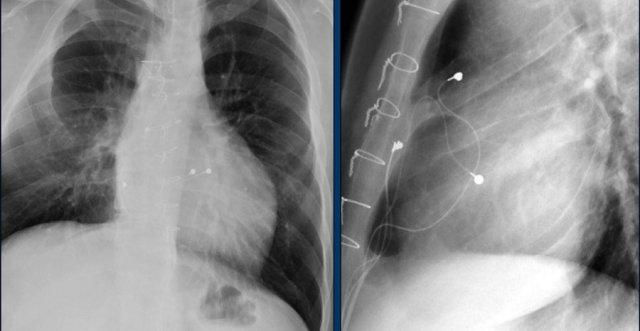

Hình ảnh được chụp ngay sau khi đặt ICD.

Có hình ảnh tràn khí màng phổi nhỏ (mũi tên).

Đây là biến chứng thường gặp nhất.